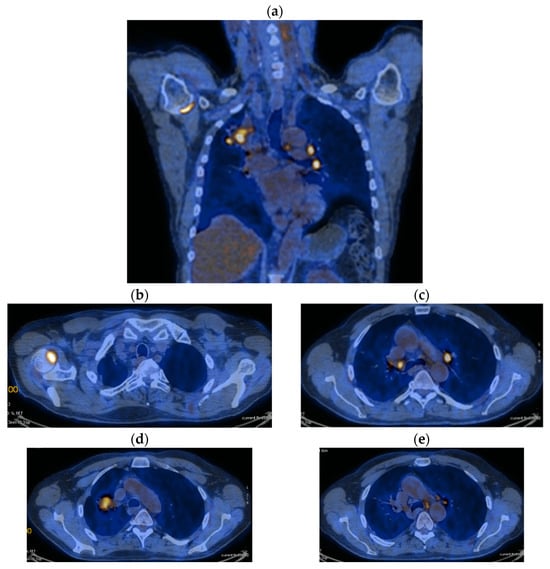

3. Case Results

| DOWNSTAGING from metastatic to locoregional stage | From cT3N3M1b(OSS) stage IVA | In cT2bN3M0, stage IIIB (without M1OSS) |